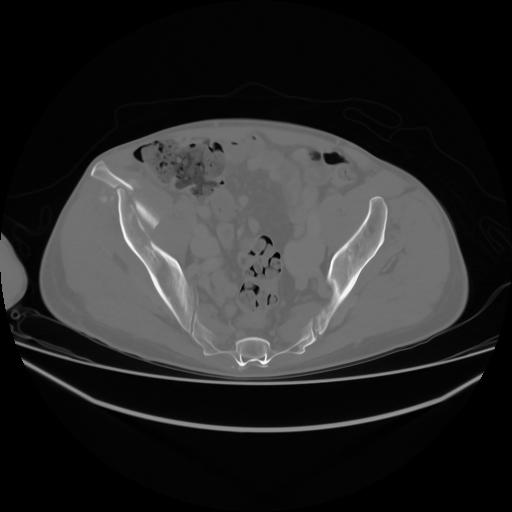

4 CUERPO,CE,Axial,3.0,CUERPO,,